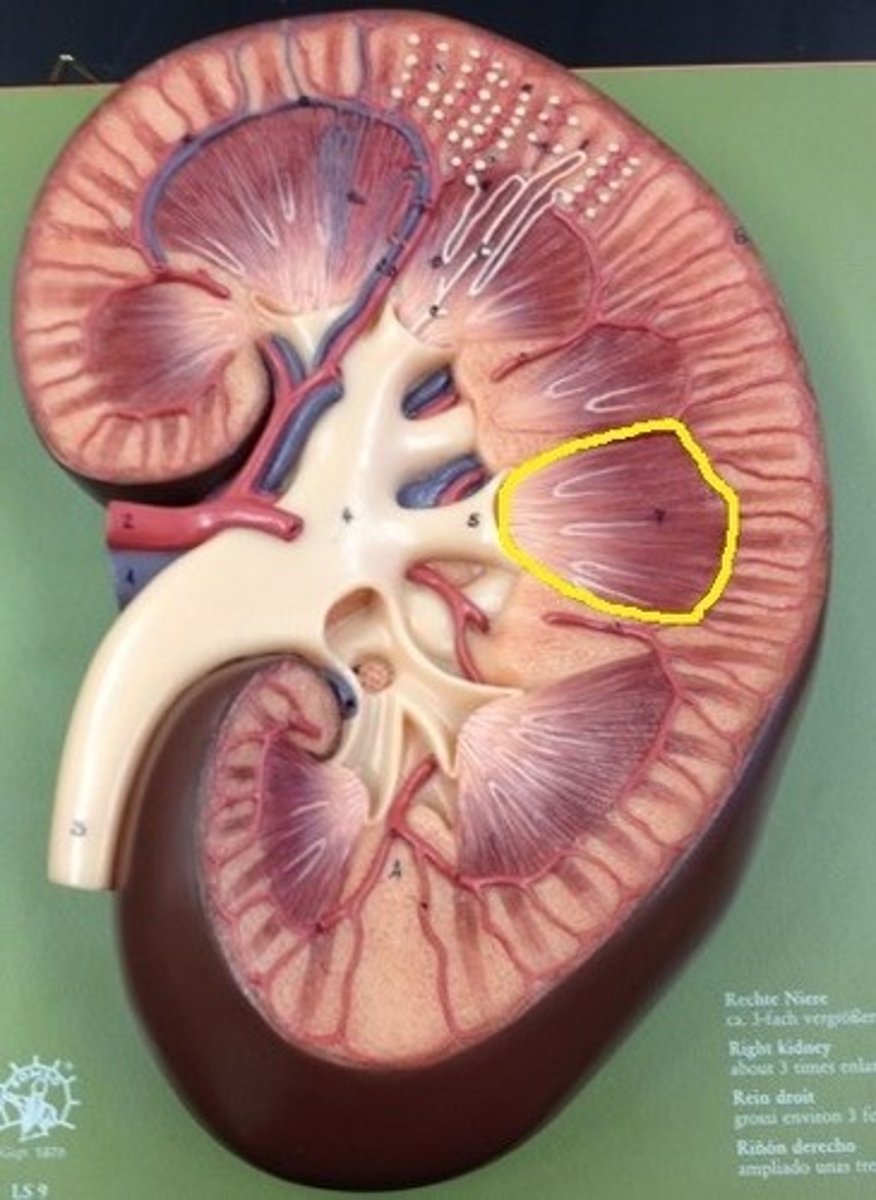

renal cortex

renal medulla

renal papilla

major calyx

minor calyx

renal pelvis

renal pyramids

renal columns